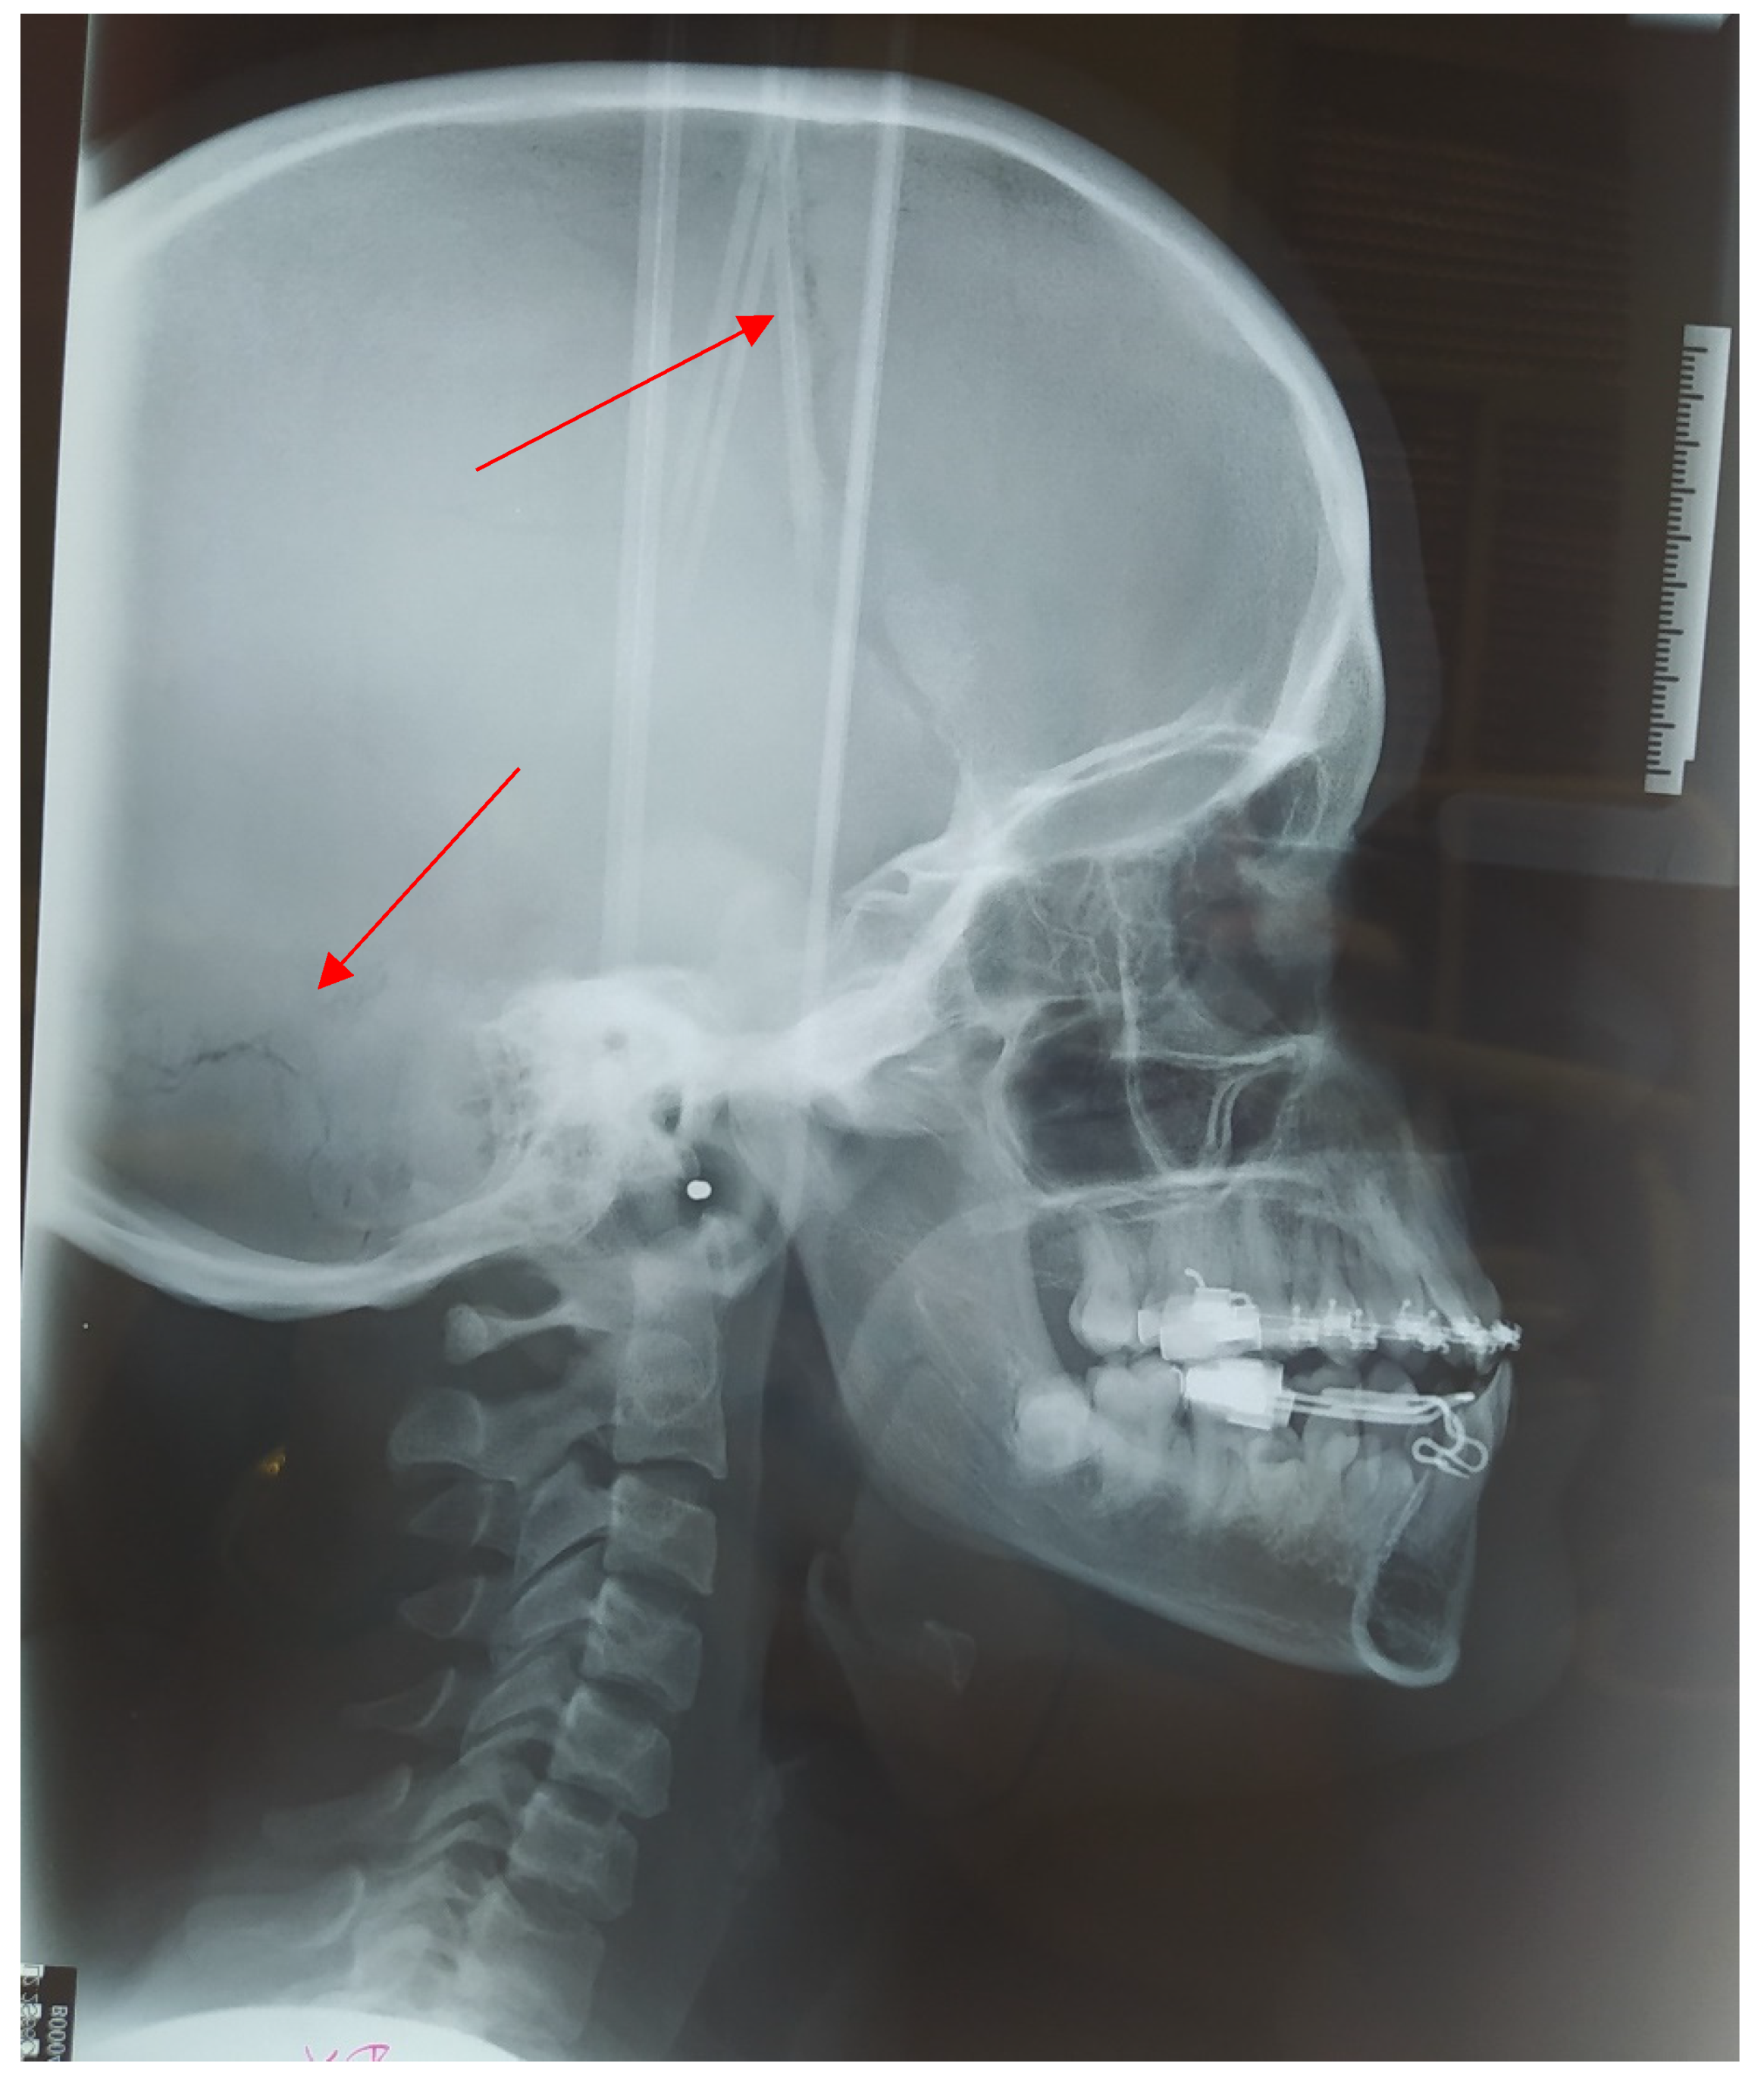

2.1. Cephalometric Analysis